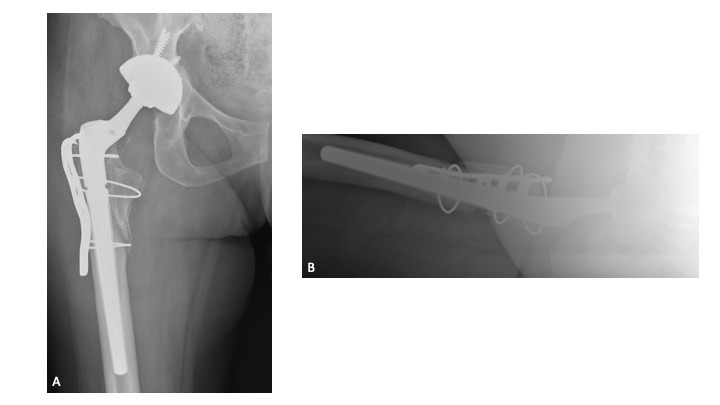

Twelve-weeks following re-implantation (2018), the patient experienced recurrent THA instability and was transitioned to our care for definitive treatment. At this time, the patient had a BMI of 24.22 kg/m2 and a past medical history of hypertension, rheumatoid arthritis, gastroparesis, hypothyroidism, and iron deficiency anemia. Relevant prescription medications included calcium carbonate, cholecalciferol, cyclobenzaprine, diltiazem, gabapentin, levothyroxine, and lisinopril. In August 2018, the patient underwent right THA acetabular revision with a porous titanium acetabular shell (56-mm) and dual mobility acetabular liner (44-mm), with four screws (30-mm x 2; 25-mm x 2) for adjuvant fixation. The existing stem was well-fixed and left in place, and a 44-mm/28-mm (+6) ceramic taper sleeve head was impacted. (Figures 4a-b) The patient followed a normal post-operative course and was ambulating pain free without assistance.